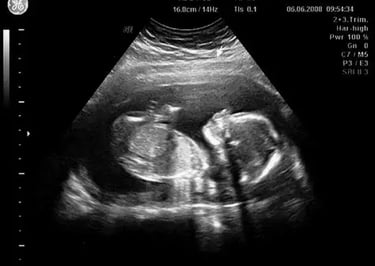

Ecografías

En IPS Santa Salud, Aguachica, Cesar, ofrecemos servicios de ecografía con tecnología de última generación, garantizando imágenes claras y diagnósticos precisos. Nuestro equipo de especialistas está capacitado para brindar una atención cercana y confiable, cuidando tu bienestar y el de tu familia.

Realizamos estudios ecográficos para diferentes necesidades médicas, asegurando resultados rápidos y confiables que apoyan tu salud integral.